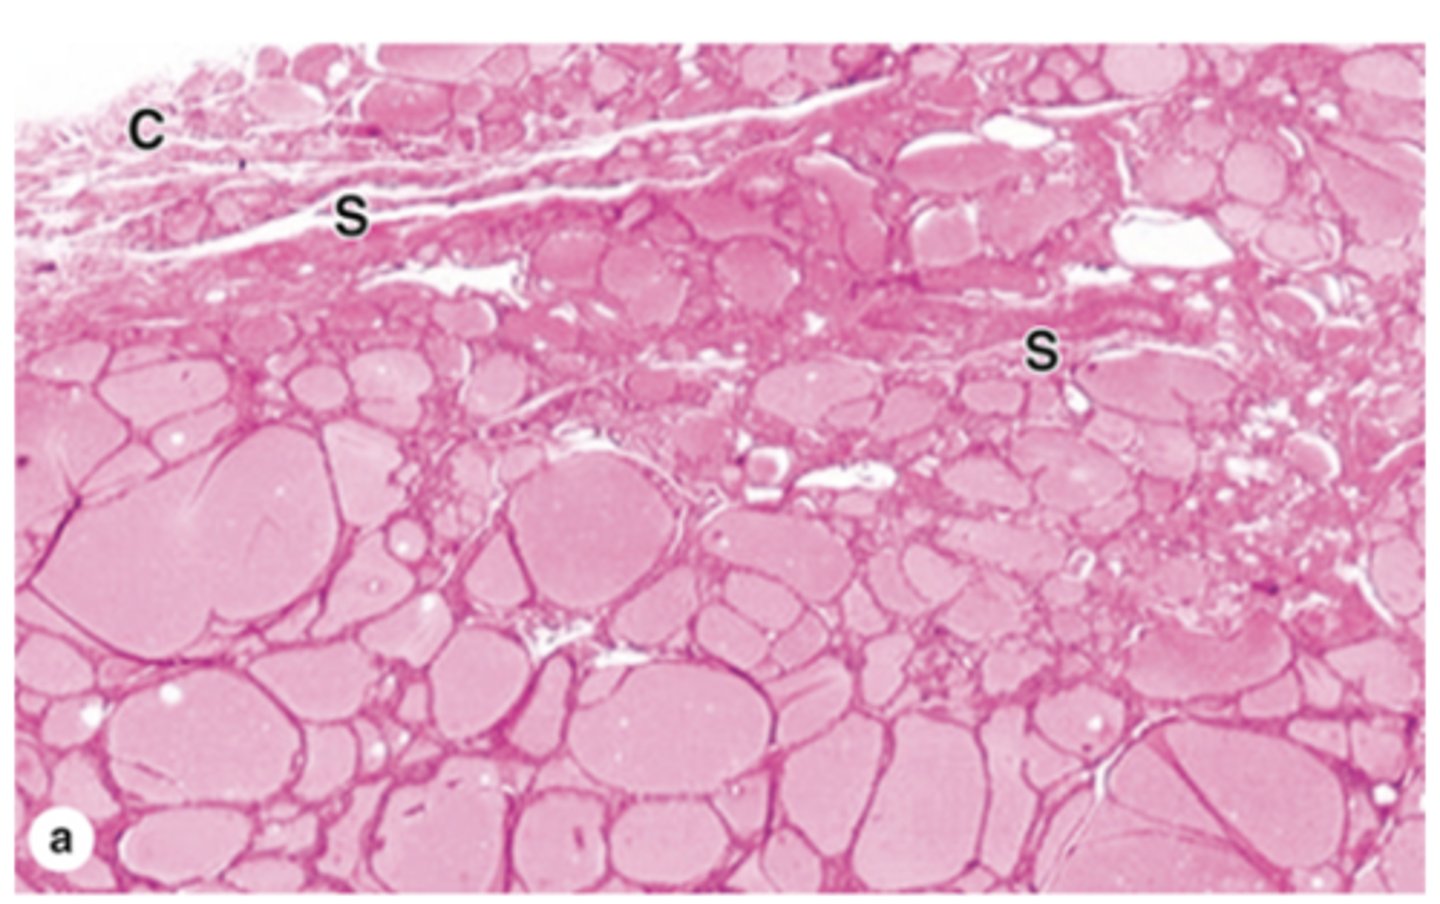

What are the adrenal glands and where are they located?

Paired, retroperitoneal organs located above the kidneys

What is the stroma of the adrenal glands composed of?

- Thick capsule of dense connective tissue

- Trabecuale of CT carrying blood vessels

- Reticular supporting CT

How is the parenchyma of the adrenal glands organized?

- Cells grouped in cords***

Two regions:

- Adrenal cortex

- Adrenal medulla

Where is the zona glomerulosa located, and what proportion of the adrenal cortex does it make up?

Just below the capsule, making up about 15% of the adrenal cortex.

What is the cellular arrangement and shape in the zona glomerulosa?

Closely packed, rounded or arched cords of columnar or pyramidal cells.